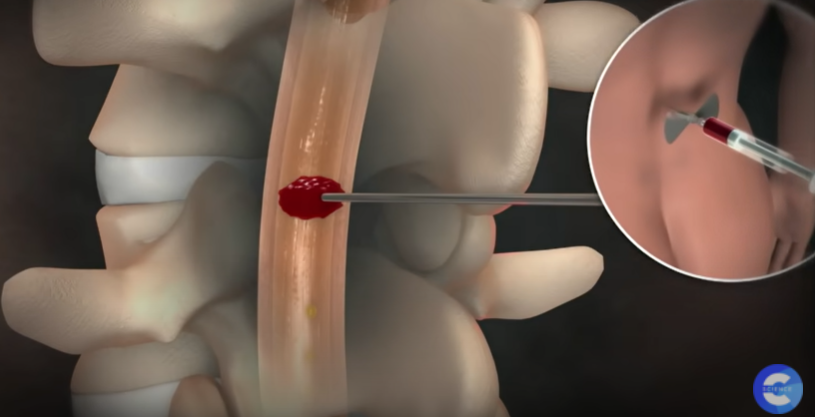

뇌동맥류 치료 : 클립 결찰술, 코일 색전술

직접 머리를 열어 뇌동맥류를 클립으로 묶어주는 경부 결찰술과

혈관을 따라 와이어를 삽입한 뇌동맥류 안쪽 공간을 가느다란 코일로 채워주는 코일 색전술이 있다.

둘 다 뇌동맥류로 가는 혈류를 차단해 파열을 막아주는 효과가 있다.

대개 개두술, 경부 결찰술을 하는 뇌수술을 받으면 굉장히 위험하고 혈관 내 수술, 즉 코일 색전술은 안전하다 생각하는데 치료법의 결정은 동맥류의 모양에 큰 영향을 받는다. 경부(동맥류가 시작하는 목 부분)가 굉장히 좁고 동맥류 자체가 크면 코일 색전술을 하기 쉽다. 반대로 경부는 넓고 동맥류의 높이는 높지 않은데 위험한 위치에 있을 경우, 코일 색전술을 하면 동맥류가 불거진 부분에 코일일 지지할 곳이 없다. 이 경우 개두술을 하고 경부 결찰술을 시행하는 것이 훨씬 안전하고 효과적이다.

- 신경외과 김종수 교수

뇌척수액 누출 두통의 치료

시술은 국소 마취제를 주사한 후에, 가느다란 관인 카테터를 척수를 싸고 있는 격막의 바깥 공간에 삽입하고

그 안으로 환자의 혈액을 주입하면 피가 응고되면서 누수를 막아 준다.

이때 새로 만들어진 뇌척수액이 채워지면서 주저앉았던 뇌가 제자리를 찾아간다.